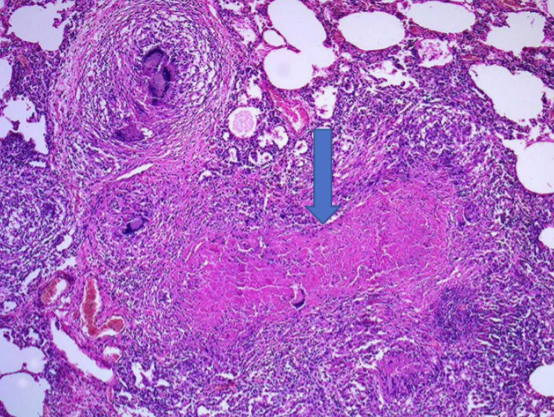

What is this?

Granuloma with caseous necrosis